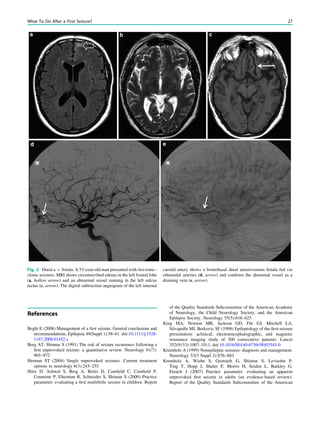

Fig. 2 Dural a. v. fistula. A 53-year-old man presented with two tonic–

clonic seizures. MRI shows circumscribed edema in the left frontal lobe

(a, hollow arrow) and an abnormal vessel running in the left sulcus

rectus (c, arrow). The digital subtraction angiogram of the left internal

carotid artery shows a frontobasal dural arteriovenous fistula fed via

ethmoidal arteries (d, arrow) and confirms the abnormal vessel as a

draining vein (e, arrow)